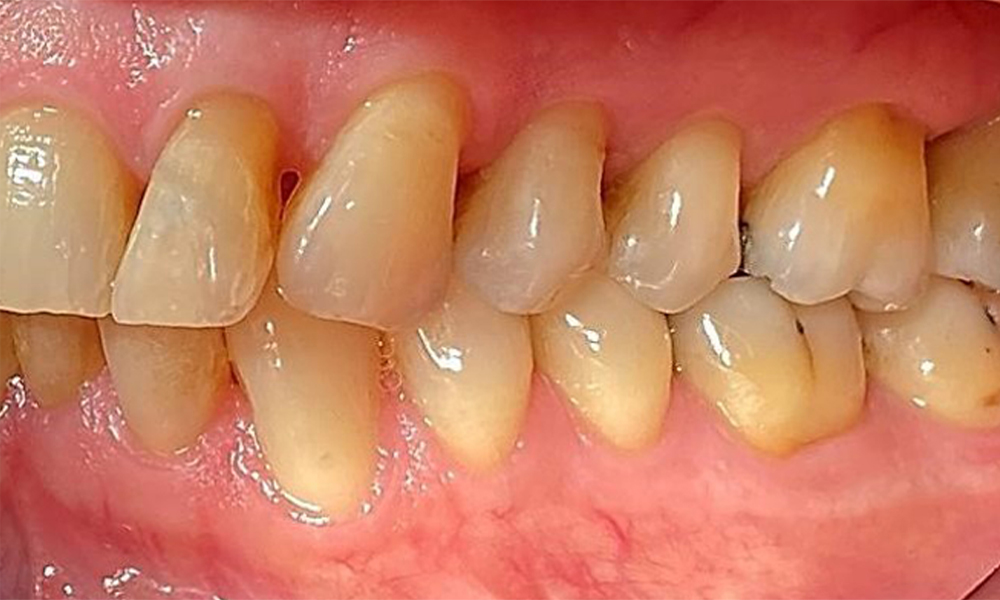

Right lateral view. Loss of the interdental papillae.

Fig. 3 Right lateral view. Loss of the interdental papillae. © Dr R. Krapf

Left lateral view including the recessions.

Fig. 4 Left lateral view including the recessions. © Dr R. Krapf

The patient has a full dentition with 28 teeth, which includes amalgam and composite fillings in the molar and premolar regions. There is a visible clinical marginal gap present on tooth 14. Tooth 27 has an adequate gold inlay. There are also generalized attritions and abrasions. (Fig. 2, Fig. 3, Fig. 4, Fig. 5, Fig. 6)

Periodontal findings

The patient has stage II, grade B periodontitis (5). At 1 to 3 mm, the clinical probing depths were within the physiological range. Localized probing depths of 5 mm were observed on the mesiopalatal aspects on both 17 and 27. There are generalized recessions of 1–3 mm with partial loss of the interdental papillae (Fig. 2, Fig. 3, Fig. 4)